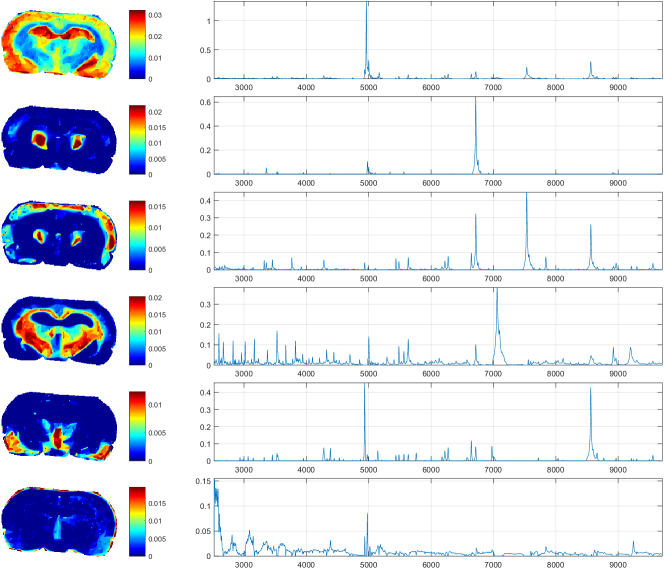

One can see immediately, that the choice of κξλsubscript𝜅𝜉𝜆\kappa_{\xi}\coloneqq\lambda for all ξ{1,,p}𝜉1𝑝\xi\in\{1,\dots,p\} is appropriate to get rid of the problematic term λ.𝜆\lambda. Hence, we obtain

00\displaystyle 0 =(KY)ξζ+XξζAξζ((KKA)ξζ+λ)absentsubscriptsuperscript𝐾𝑌𝜉𝜁subscript𝑋𝜉𝜁subscript𝐴𝜉𝜁subscriptsuperscript𝐾𝐾𝐴𝜉𝜁𝜆\displaystyle=-(K^{\intercal}Y)_{\xi\zeta}+\dfrac{X_{\xi\zeta}}{A_{\xi\zeta}}\left((K^{\intercal}KA)_{\xi\zeta}+\lambda\right)

+σ𝑿,1k=1pWkζ(XξζAξζ(AW)ξkδξk)+σ𝑿,2(XξζWξζ)subscript𝜎𝑿1superscriptsubscript𝑘1𝑝subscript𝑊𝑘𝜁subscript𝑋𝜉𝜁subscript𝐴𝜉𝜁subscript𝐴superscript𝑊𝜉𝑘subscript𝛿𝜉𝑘subscript𝜎𝑿2subscript𝑋𝜉𝜁subscript𝑊𝜉𝜁\displaystyle+\sigma_{\bm{\mathit{X}},1}\sum_{k=1}^{p}W_{k\zeta}\left(\dfrac{X_{\xi\zeta}}{A_{\xi\zeta}}(AW^{\intercal})_{\xi k}-\delta_{\xi k}\right)+\sigma_{\bm{\mathit{X}},2}(X_{\xi\zeta}-W_{\xi\zeta})

+ρβξi=1nYiζ(XξζAξζ(YAβ)iui)+νXξζ.𝜌subscript𝛽𝜉superscriptsubscript𝑖1𝑛subscript𝑌𝑖𝜁subscript𝑋𝜉𝜁subscript𝐴𝜉𝜁subscript𝑌superscript𝐴𝛽𝑖subscript𝑢𝑖𝜈subscript𝑋𝜉𝜁\displaystyle+\rho\beta_{\xi}\sum_{i=1}^{n}Y_{i\zeta}\left(\dfrac{X_{\xi\zeta}}{A_{\xi\zeta}}(YA^{\intercal}\beta)_{i}-u_{i}\right)+\nu X_{\xi\zeta}.

Reordering the terms leads to

(KY)ξζ+(σ𝑿,1+σ𝑿,2)Wξζ+ρβξ(Yu)ζsubscriptsuperscript𝐾𝑌𝜉𝜁subscript𝜎𝑿1subscript𝜎𝑿2subscript𝑊𝜉𝜁𝜌subscript𝛽𝜉subscriptsuperscript𝑌𝑢𝜁\displaystyle(K^{\intercal}Y)_{\xi\zeta}+(\sigma_{\bm{\mathit{X}},1}+\sigma_{\bm{\mathit{X}},2})W_{\xi\zeta}+\rho\beta_{\xi}(Y^{\intercal}u)_{\zeta}